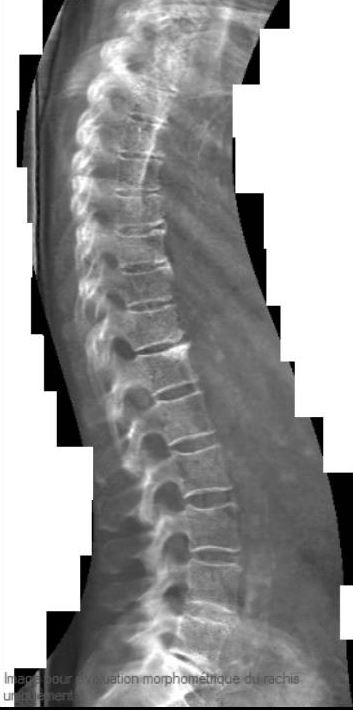

Lors de la mesure de la densitométrie osseuse, il est possible d’obtenir une image de la colonne dorsolombaire de profil en quelques minutes. Cet examen nous permet d’observer les vertèbres depuis la quatrième dorsale jusqu’à la cinquième lombaire. L’examen est trente fois moins irradiant qu’une radiographie standard de la colonne.

Le but est non seulement de rechercher une fracture, mais également de quantifier la sévérité de la fracture. Il existe trois grades, de 1 à 3, du moins sévère au plus sévère. Plus il y a de fractures, plus le grade est sévère, et plus l’ostéoporose est grave. Si les fractures de grade 2 et 3 sont plus faciles à diagnostiquer, il est souvent nécessaire de compléter l’examen par une radiographie standard de la colonne lorsque l’on suspecte une fracture de grade 1. Il est donc possible que l’on vous propose de compléter la morphométrie de la colonne par une radiographie. Dans certaines situations, comme une cyphoscoliose sévère par exemple, l’interprétation de l’examen peut être difficile, voire impossible.